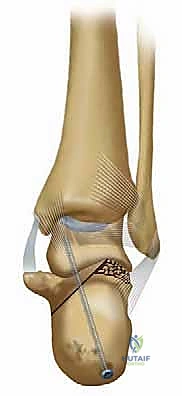

عظم العقب هو عظمة إسفنجية (Cancellous bone) ذات قشرة خارجية رقيقة. هذا التكوين يجعله قادراً على امتصاص الصدمات، ولكنه في نفس الوقت يجعله عرضة للتهشم والانضغاط عند التعرض لقوة محورية شديدة. يتكون العظم من عدة أجزاء رئيسية:

1. الحدبة الخلفية (Posterior Tuberosity): نقطة ارتكاز وتر أخيل.

2. السطح المفصلي الخلفي (Posterior Articular Facet): الجزء الأهم الذي يتمفصل مع عظم الكاحل (Talus) لتكوين المفصل تحت الكاحل.

3. المعلاق الكاحلي (Sustentaculum Tali): بروز عظمي داخلي يدعم عظم الكاحل وتمر تحته أوتار وأعصاب هامة.

4. العملية الأمامية (Anterior Process): تتمفصل مع العظم النردي (Cuboid).

المفصل تحت الكاحل هو مفصل زلالي معقد يسمح بحركتي الانقلاب الداخلي (Inversion) والانقلاب الخارجي (Eversion). أي خلل في تطابق الأسطح الغضروفية لهذا المفصل بمقدار ملليمترات قليلة يؤدي إلى احتكاك غير طبيعي، تآكل سريع للغضروف، وتطور التهاب المفاصل التنكسي (Osteoarthritis) المؤلم.

2. التوسع الجانبي والانحشار الشظوي العقباني (Fibulocalcaneal Impingement)

عندما يتهشم عظم العقب، فإنه ينضغط من الأعلى للأسفل، مما يؤدي إلى توسعه وانتشاره نحو الخارج (Lateral Wall Blowout). عندما يلتئم العظم على هذا النحو، يصبح الكعب أعرض بكثير من الطبيعي. هذا الجدار الجانبي المتوسع ينحشر مباشرة ضد الجزء السفلي من عظم الشظية (الكَعب الجانبي - Lateral Malleolus). هذا الانحشار العظمي يسبب ألماً حاداً عند الوقوف والمشي، ويجعل من المستحيل تقريباً ارتداء الأحذية المغلقة.